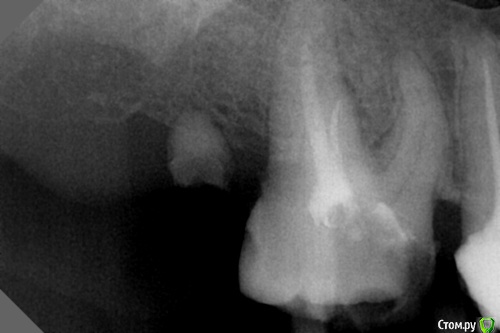

dr.Dre Опубликовано 24 мая, 2016 Поделиться Опубликовано 24 мая, 2016 Добрый день коллеги,16 зуб перелечивание дистальный канал прошел ,небный до половины,мб ни ультразвуком ни С пилотами не идет.Что делать в данной ситуации ? Ссылка на комментарий

vse32 Опубликовано 24 мая, 2016 Поделиться Опубликовано 24 мая, 2016 Добрый день коллеги,16 зуб перелечивание дистальный канал прошел ,небный до половины,мб ни ультразвуком ни С пилотами не идет.Что делать в данной ситуации ?Либо продолжить в другой день, либо отдать другому врачу. Канал то явно есть, просто у Вас "глаз замылился".Канал от устья сильно под углом - возможно в этом проблема, за устье цепляетесь, а дальше направление инструмента не позволяет идти. Попробуйте положить инструмент сильно дистально ручкой. УЗ пробовали устье чуть чуть пройти?А мне кажется, или там надо и МБ1 и МБ2 искать? Ссылка на комментарий

St. Опубликовано 24 мая, 2016 Поделиться Опубликовано 24 мая, 2016 Расширьтесь и ищите медиальнее, по снимку ушли слишком к фуркации. 1 Ссылка на комментарий